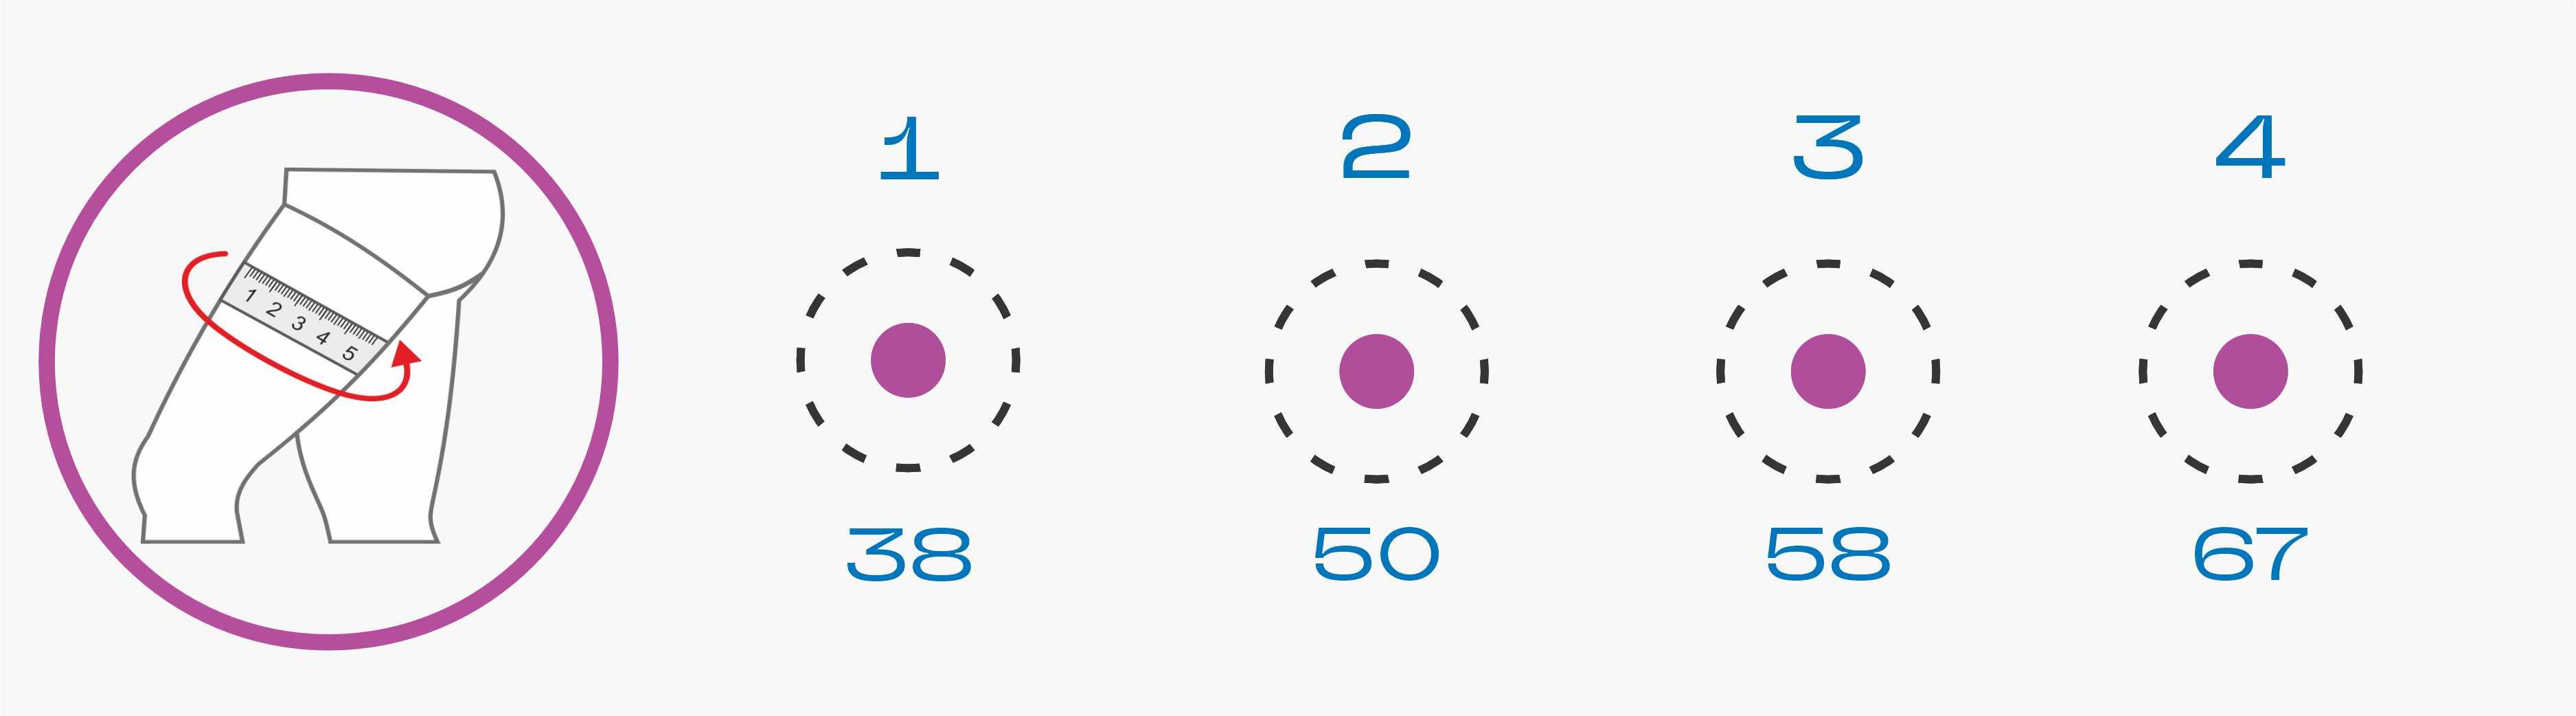

Тутор коленного сустава Тутор или иммобилизатор коленного сустава предназначен для обездвиживания ноги и коленного сустава и представляет из себя жесткий ортез и заменяет гипс, во многом превосходя его по функциональности. Тутор позволяет индивидуально отрегулировать фиксацию колена и костей при переломах без смещения или разрывах связок, обеспечивает более жесткую и анатомическую фиксацию, чем гипс. Тутор для колена регулируется индивидуально, его можно снимать, чтобы постирать или чтобы провести гигиенические процедуры, позволяет избежать раздражения и пролежней, а также он отличается лучшим кровоснабжением ноги, в сравнении с гипсом. Смотрите инструкцию по применению внутри упаковки.